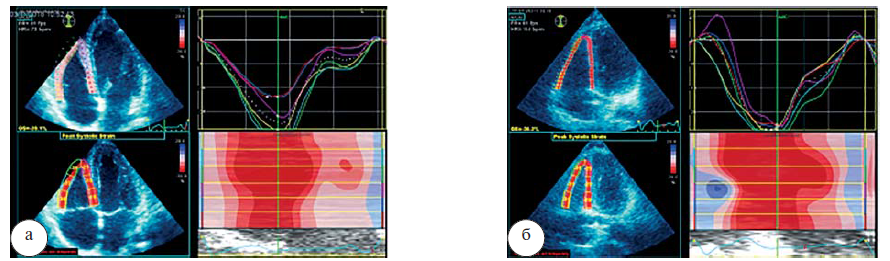

ФВ ПЖ в 3D-режиме, как и КДО и КСО ПЖ в покое в группах статистически не различалась, и её значения были в пределах нормы, представленной в рекомендациях ASE/EACVI (2015), т. е. ФВ ПЖ составляла не менее 45% (рис 1).

Рис. 1. Результаты ЭхоКГ здорового мужчины 35 лет в покое (а): ФВ ПЖ в 3D-режиме=55,4%; пациента К. 35 лет, страдающего саркоидозом легких II стадии, в покое (б): ФВ ПЖ в 3D-режиме=52,1%